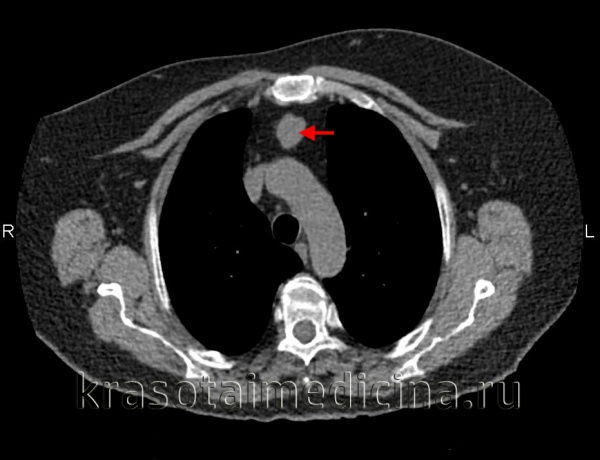

Лимфомы медиастинальной локализации не всегда диагностируются при рентгенологическом обследовании. Компьютерная томография, более детально, чем обзорная рентгенография позволяет рассмотреть конгломерат опухоли, увеличение лимфоузлов средостения, вовлечение паратрахеальных, трахеобронхиальных, прикорневых лимфатических узлов. Диагностическая значимость магнитно-резонансной томографии в верификации лимфом средостения признается не всеми авторами.

КТ ОГК. Объемное образование в средостении (патологически измененный лимфоузел), подтвержденная лимфома.